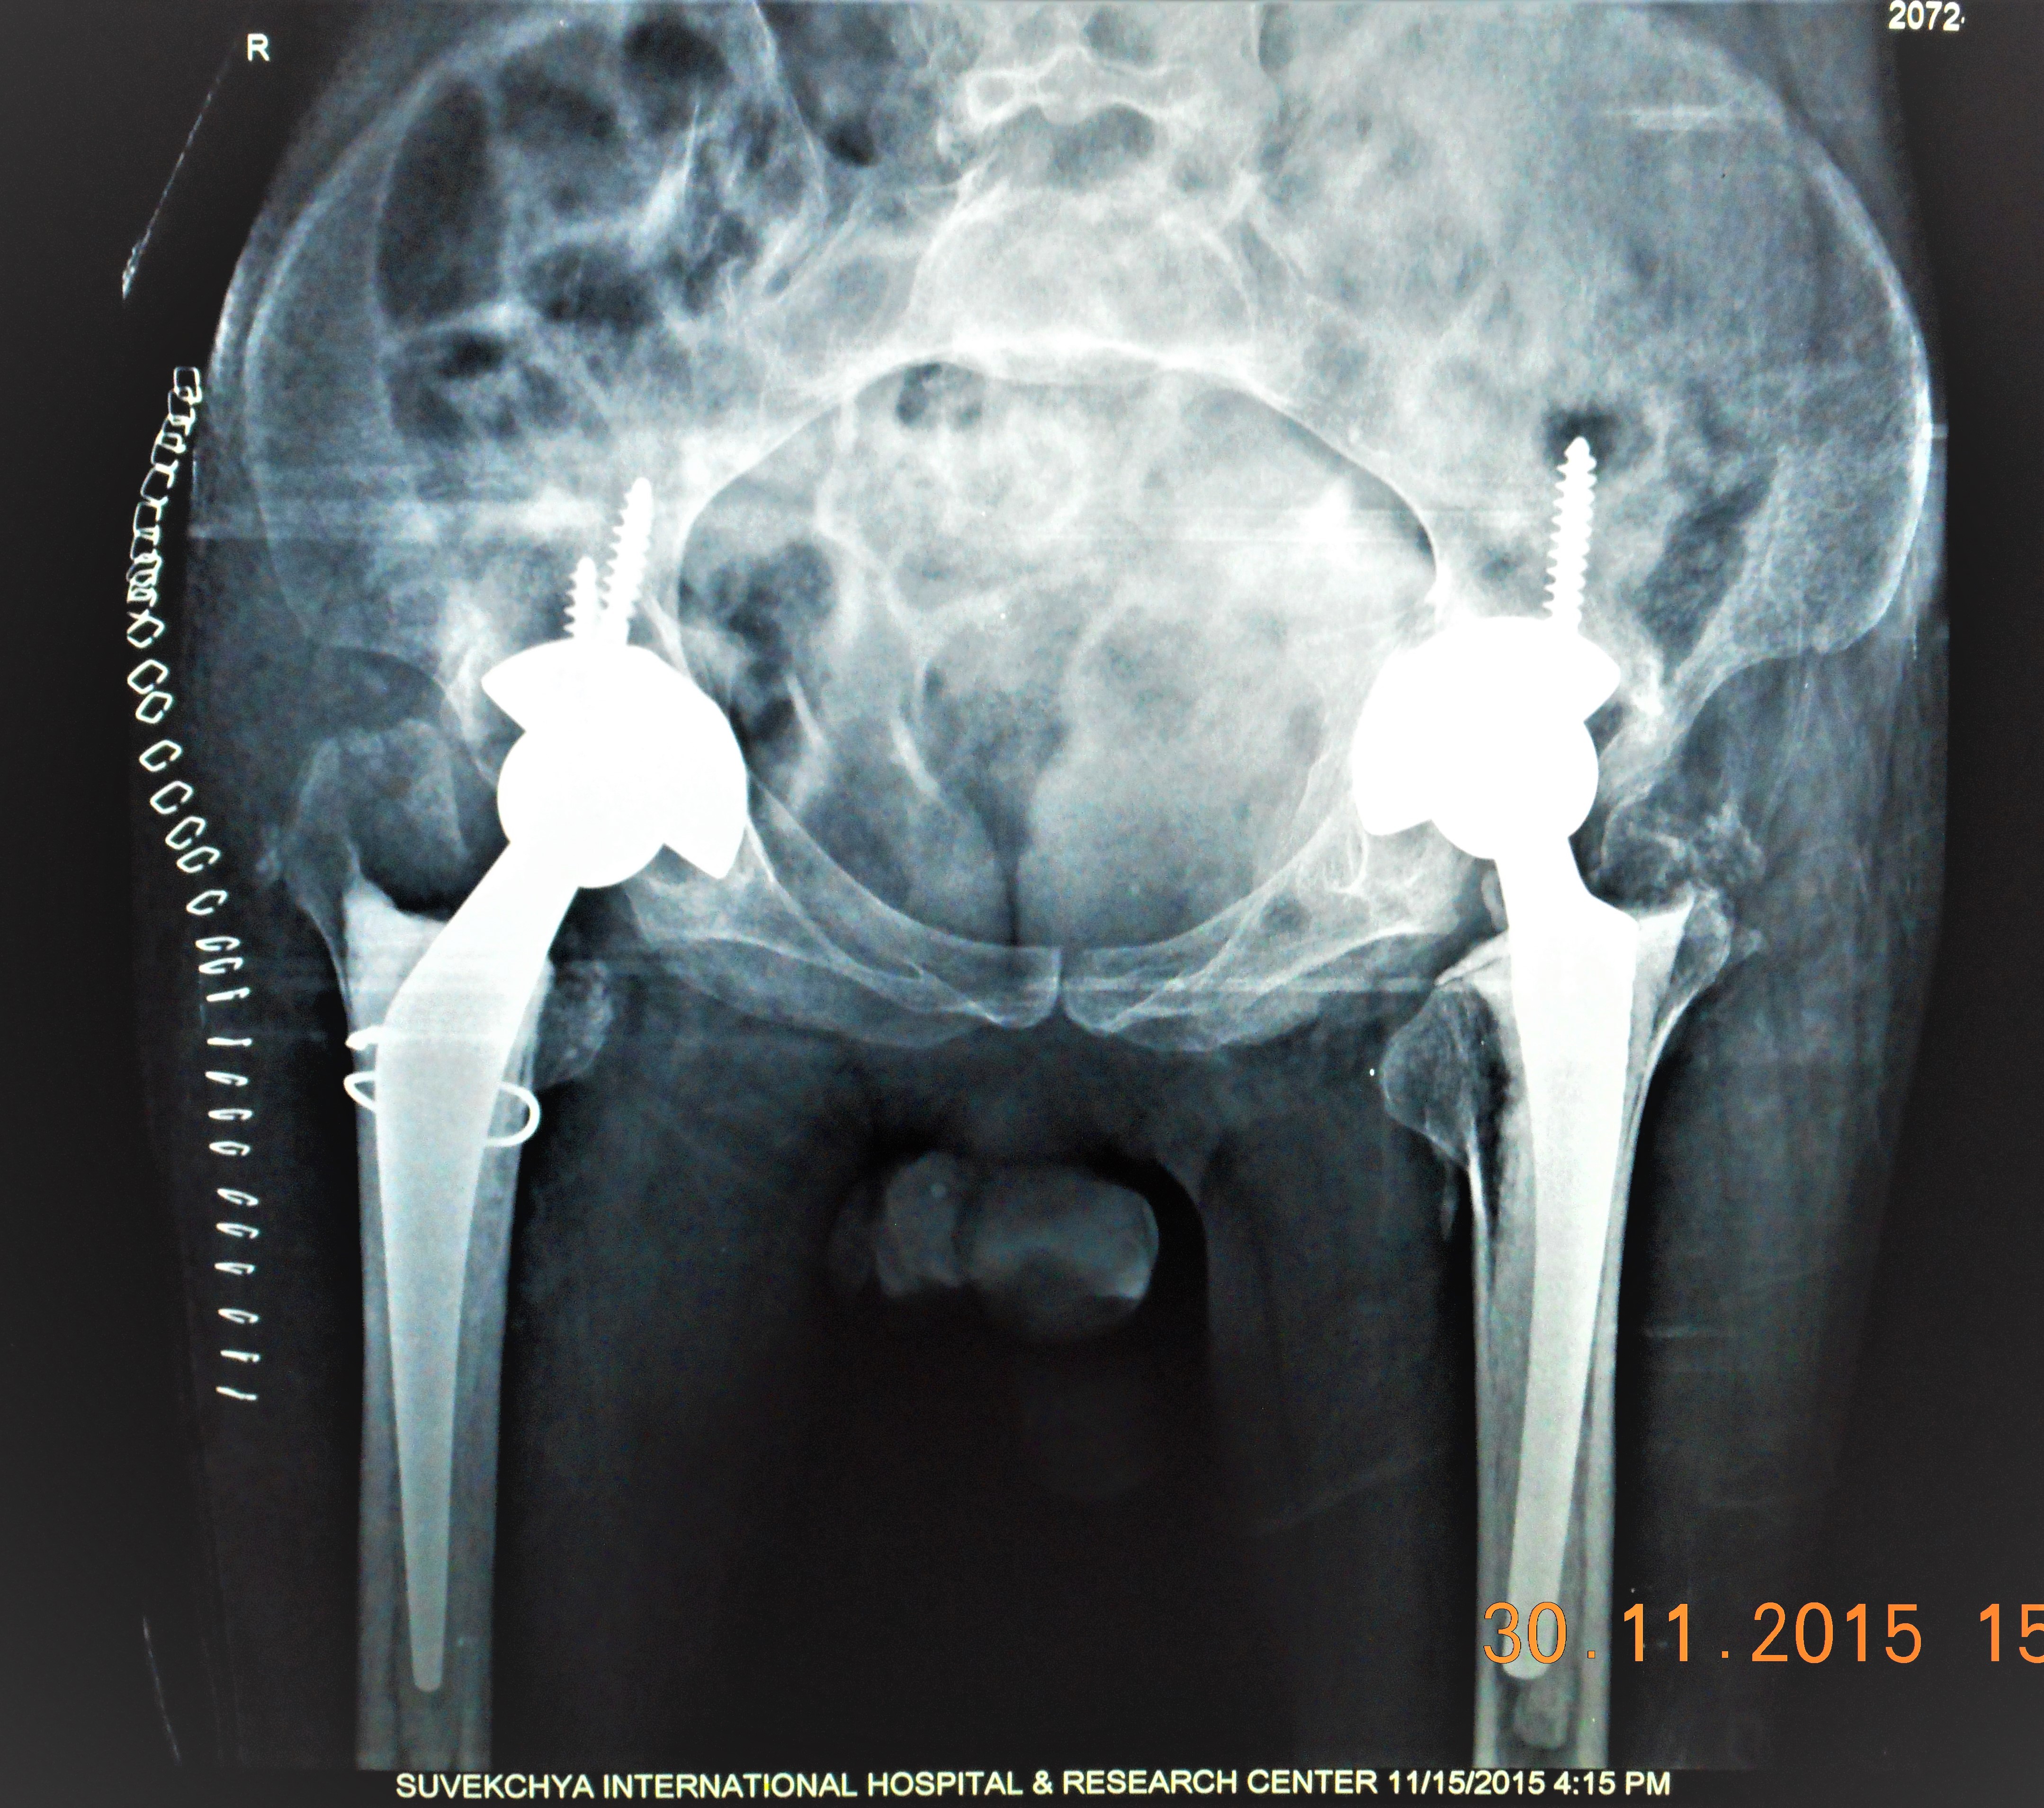

- Hip Replacement Operation

- Post Op X Ray